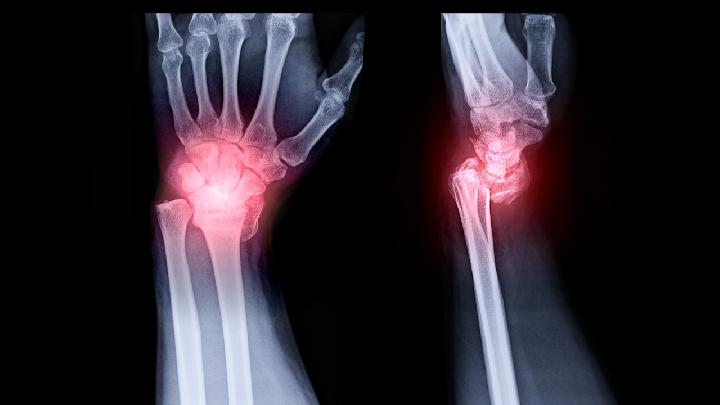

银屑病性关节炎

银屑病性关节炎的西医疗法